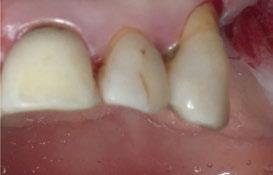

A partir del estudio radiológico y de las imágenes fotográficas podemos observar edentulismo de 17, 15, 14, 12,

25, 26, 28, 37, 38, 47 y 48. Presentaba corona desajustada en 13 con extensión en 12, implantes en 35-36, 45-46, con coronas ferulizadas en 35-36, 45-46, y dientes anteriores superiores con enfermedad periodontal Grado IV.

2. Exploración de tejidos blandos

El paciente presentaba biotipo periodontal grueso, con márgenes asimétricos, con recesiones gingivales a nivel de 11 y 13 y pérdida de tejidos blandos interproximales.